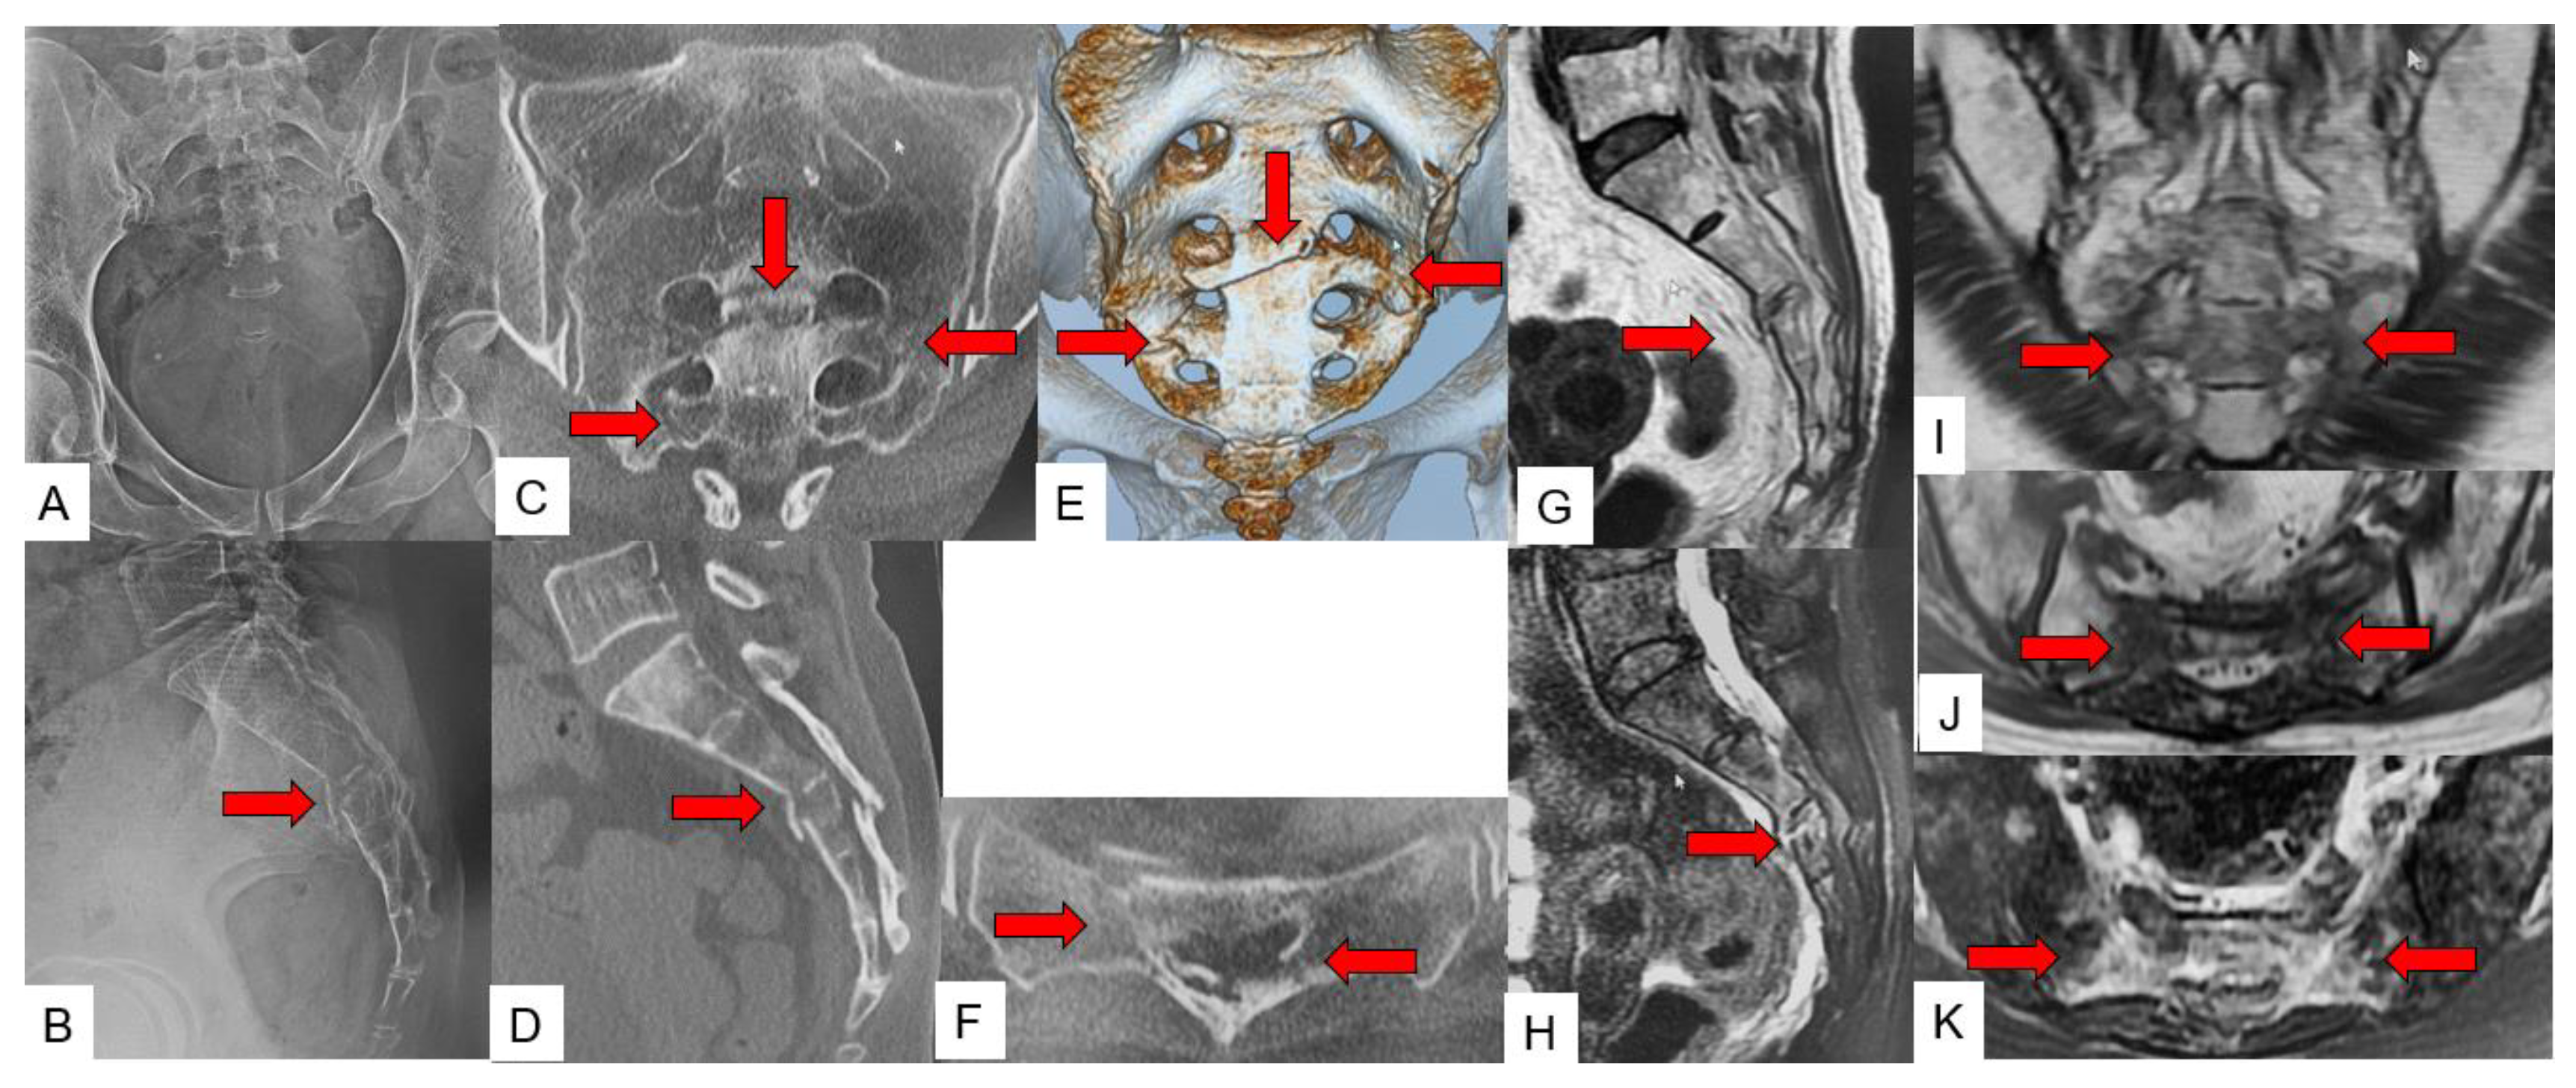

3.3. SIF Fracture Pattern

3.4. Typical SIF Case